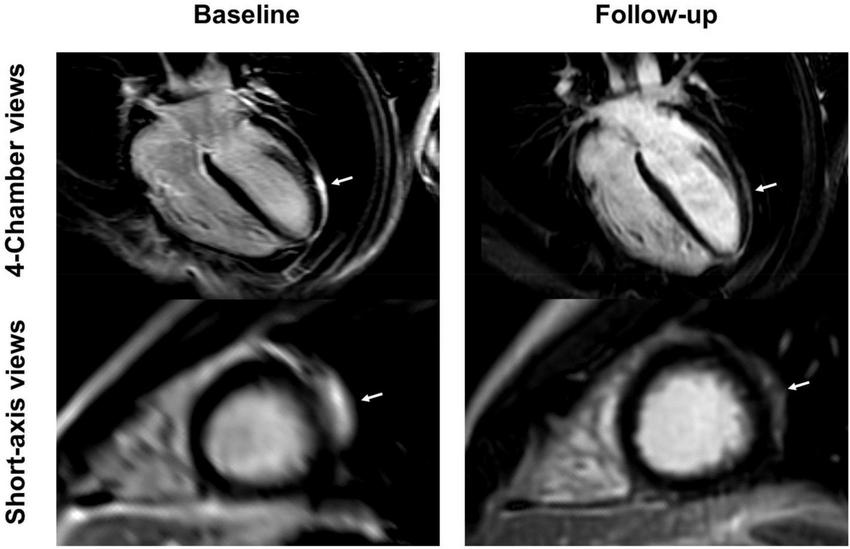

FIGURE 7

4-chamber and short-axis late gadolinium enhancement (LGE) views of a 15-year-old male after receiving the second dose of the Pfizer/BioNTech vaccine. Subepicardial and pericardial LGE at the apical lateral wall (arrows) shows a marked decrease at the 9-month follow-up with residual findings. Resolution of chest pain at follow-up was accompanied by new onset of occasional exertional dyspnea.